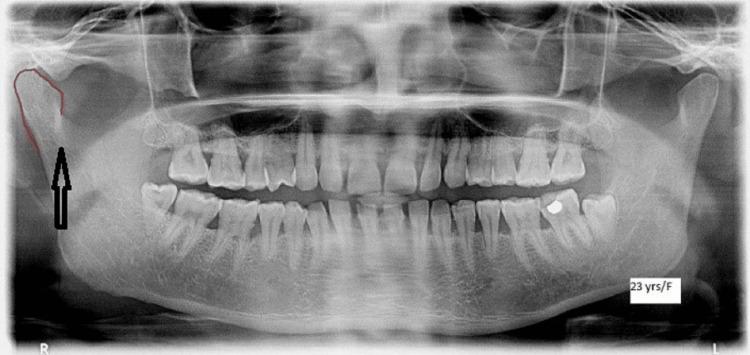

The aim of this study is to assess morphological variations of the coronoid process, condyle, and sigmoid notch as an adjunct in personal identification using orthopantomograms among the North Indian population.

METHODOLOGY

The study sample (n=240) was distributed into four age groups: Group I: 30 males and 30 females aged 10-19 years, Group II: 30 males and 30 females aged 20-29 years, Group III: 30 males and 30 females aged 30-39 years, and Group IV: 30 males and 30 females aged 40-59 years. All were subjected to panoramic radiographs. The different morphological forms of the coronoid process, condyle, and sigmoid notch were evaluated.

RESULTS

The results showed that across all age groups, angular condyles were the most common kind of condyle in males, followed by round and convex types. The present study found that the coronoid process typically takes on a triangle shape across all ages and sexes. Additionally, the vast majority of cases were triangular on both sides, and this was true across both sexes. It was found in this study that the sigmoid notch most commonly took the form of a larger notch, followed by a rounder notch.

CONCLUSION

Using panoramic photos to portray the different morphologies of the coronoid process, condyle, and sigmoid notch can be a much simpler and faster method of identifying an individual, especially in the event of a mass disaster, so long as antemortem data are kept. The method of radiographic identification of individuals has recently gained prominence due to its efficacy. Radiographs like these can be invaluable in forensic dentistry, where they can help unearth previously hidden evidence if premortem records are retained. As a potential approach for individual identification among our population, panoramic radiographs were used to investigate the varying morphological forms of the coronoid process, condyle, and sigmoid notch.